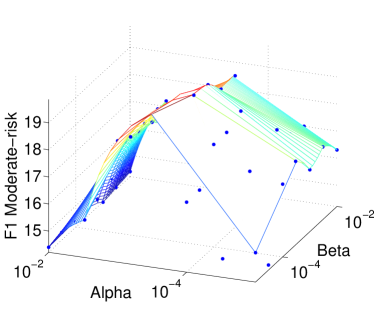

7.3.1 Sensitivity to Hyperparameters

There are two hyperparameters in our objective function in Eq. (8): the -norm regularization factor and the network regularization factor . These two factors serve different purposes: The -norm regularization as an embedded feature selection mechanism, and the network regularization for stabilizing the models. To investigate the sensitivity of the final performance against these hyperparameters, we perform a grid search in the set {,,,,,} for each. Figs. 4(a,b) report the -score measures for the moderate-risk ( class) and high-risk ( class) outcomes within months under cumulative classifiers (Section 5.1.1). The -scores in both risk classes critically depends on but are relatively stable against . The former dependency is expected: large generally leads to sparser models, and thus less overfitting. When the sparsity reaches the right level – at – the predictive power peaks. The small effect of on the performance is interesting but not surprising. As large forces linked features to have similar weights, the feature influence is rearranged but overall their total effect remains largely unchanged. Thus in what follows, unless specified otherwise, we fix the sparsity hyperparameter as for all classifiers.

Our work demonstrated that model stability for high-dimensional problems could be significantly enhanced by exploiting known relations between features. This validates our intuition that prior knowledge would help as it is independent of data sampling procedures. Consistent with prior studies, our results confirm that such prior relations, as realized in feature network regularization, improve the generalization when no other regularization schemes are in place [20][56]. However, interestingly, when combined with lasso, their effect on predictive performance is insignificant, as shown in Fig. 4. It is surprising because model stability could potentially lead to better prediction stability, and which is a sufficient condition for generalization [9, 49]. This suggests that the two stability concepts may not be strongly correlated, as it is known that random forests, for example, can generate very different tree ensembles (model instability) but the end results can be quite stable (prediction stability).